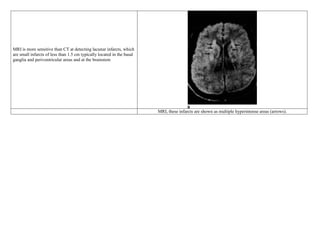

MRI is more sensitive than CT at detecting lacunar infarcts, which

are small infarcts of less than 1.5 cm typically located in the basal

ganglia and periventricular areas and at the brainstem

MRI, these infarcts are shown as multiple hyperintense areas (arrows).